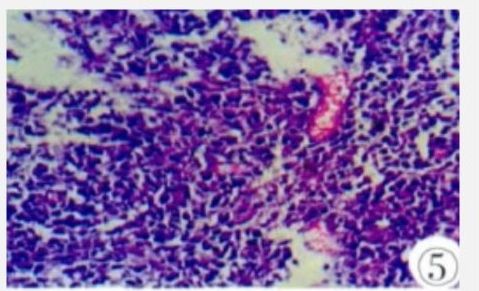

手术及病理所见:在全麻下行膀胱镜检,膀胱镜示:膀胱右侧壁黏膜面不光滑,可见双侧输尿管开口正常并喷尿。行经尿道离子束刀膀胱肿瘤切除术。术后病理回报:巨检:灰白相间灰黄色碎组织,大小共2mm×2mm×3mm;镜下:大量大小较一致的异型细胞,排列密集,细胞核圆形或卵圆形、泡状,核仁明显,2~4个靠近核膜,胞质较少,嗜双色或嗜碱性,可见核分裂,并见多灶性不规则坏死灶(图5)。

图5 镜下(HE):大量大小较一致的异型细胞,排列密集,胞质较少,嗜双色或嗜碱性,可见核分裂。图6免疫组化CD20(+)。免疫组化结果回报:CK(-)、CK20(-)、CK7(-)、P63(-)、LCA(+)、Bcl-6(+)、Bcl-2(+>50%)、CD10(-)、CD20(+)(图6)、CD21(+)、CD23(-)、CD3(-)、CD5(+)、CyclinD1(-)、EBER(-)、MUM-1(+)、c-myc(+>40%)、ki-67(+>80%)。病理诊断:膀胱肿物活检示弥漫大B细胞淋巴瘤(生发中心外活化B细胞来源)。结合病史、病理、免疫组化及相关辅助检查,临床诊断为弥漫大B细胞淋巴瘤(生发中心外活化B细胞来源)Ⅳ期B组,IPI评分3分。术后转入血液科予以R-CHOP方案联合化疗(美罗华600mgd1、环磷酰胺1200mg、吡柔比星40mgd1-2、长春新碱2mgd1、醋酸泼尼松100mgd1-5)。截止目前(2017年5月),患者已接受4个周期化疗,一般状态较好,生命体征较为平稳,症状缓解。